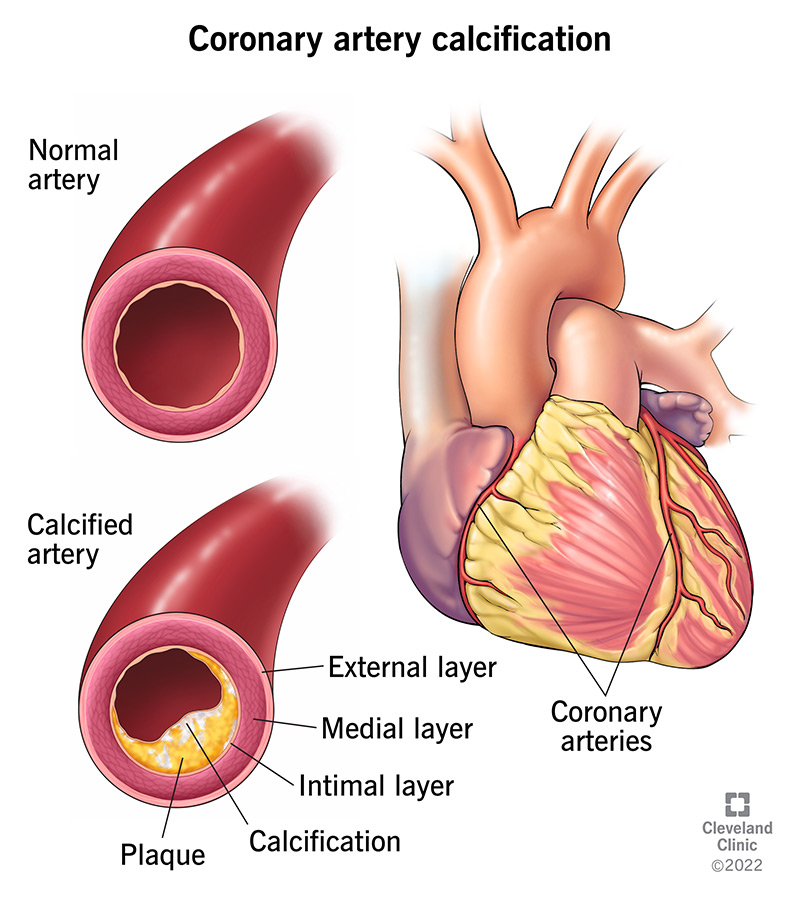

Calcium Plaque Build-Up in the Arteries | Healthfully

how dangerous is a high calcium score – Berta Montalvo

Severe coronary artery calcification in a patient with end stage renal …